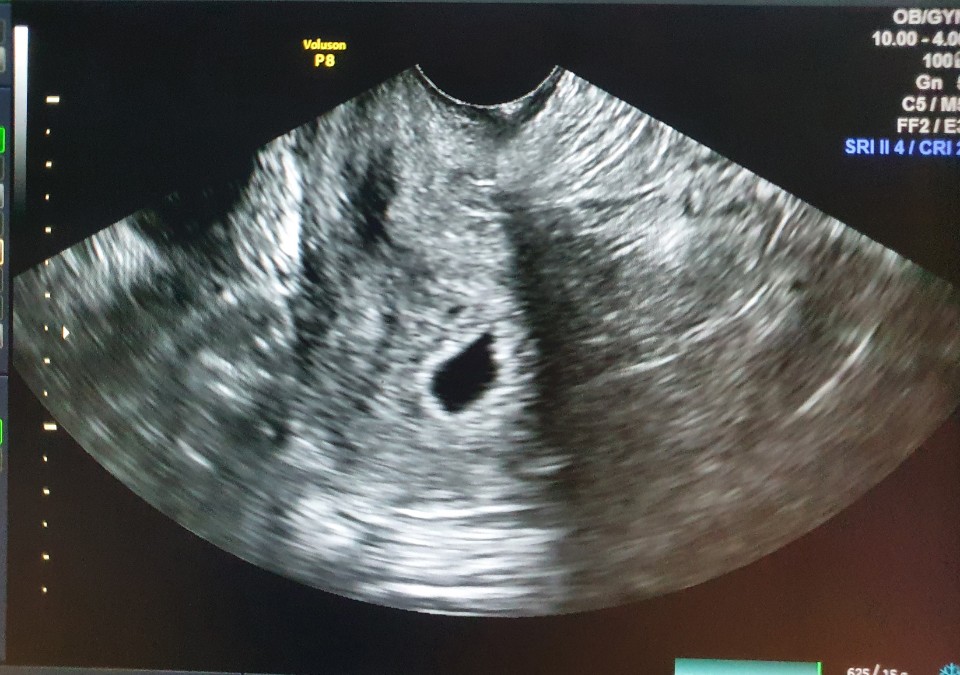

작년 3월9일에 결혼했던 제 친 형 , 형수님에게 행복이(태명)가 찾아왔어요!!